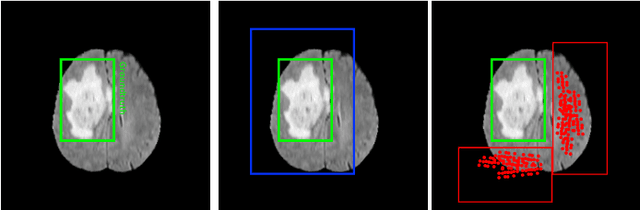

Abstract:In recent years, deep neural networks have achieved state-of-the-art performance in a variety of recognition and segmentation tasks in medical imaging including brain tumor segmentation. We investigate that segmenting a brain tumor is facing to the imbalanced data problem where the number of pixels belonging to the background class (non tumor pixel) is much larger than the number of pixels belonging to the foreground class (tumor pixel). To address this problem, we propose a multi-task network which is formed as a cascaded structure. Our model consists of two targets, i.e., (i) effectively differentiate the brain tumor regions and (ii) estimate the brain tumor mask. The first objective is performed by our proposed contextual brain tumor detection network, which plays a role of an attention gate and focuses on the region around brain tumor only while ignoring the far neighbor background which is less correlated to the tumor. The second objective is built upon a 3D atrous residual network and under an encode-decode network in order to effectively segment both large and small objects (brain tumor). Our 3D atrous residual network is designed with a skip connection to enables the gradient from the deep layers to be directly propagated to shallow layers, thus, features of different depths are preserved and used for refining each other. In order to incorporate larger contextual information from volume MRI data, our network utilizes the 3D atrous convolution with various kernel sizes, which enlarges the receptive field of filters. Our proposed network has been evaluated on various datasets including BRATS2015, BRATS2017 and BRATS2018 datasets with both validation set and testing set. Our performance has been benchmarked by both region-based metrics and surface-based metrics. We also have conducted comparisons against state-of-the-art approaches.